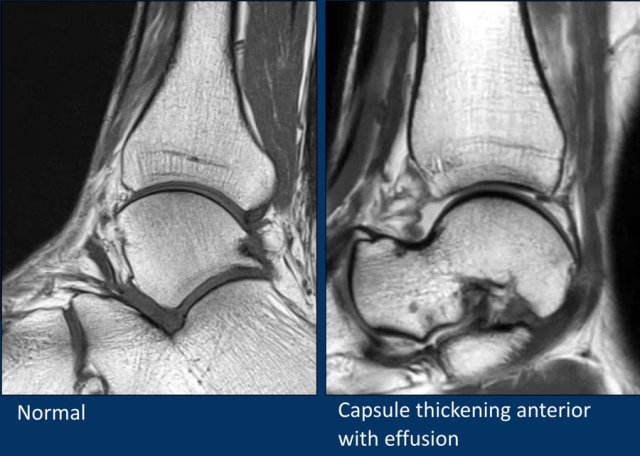

Capsular thickening

The ankle joint is lined by the joint capsule.

When the capsule is thickened, it may cause impingement or synovitis, which can be seen in the image in the middle.

The capsule thickening can be posttraumatic or postoperative.